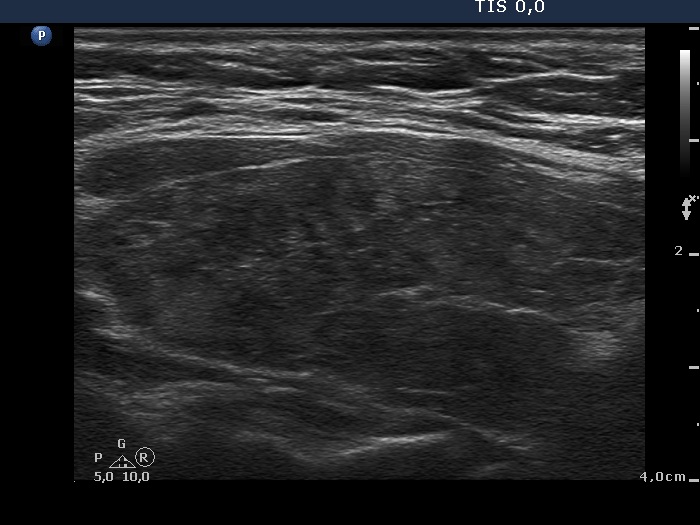

Second examination seven years later (second row of images):

Clinical presentation: The patient requested the evaluation because of complaints suggesting hypothyroidism.

Palpation: unchanged.

Laboratory tests: TSH 6.81 mIU/L on daily 50 microgram levothyroxine.

Ultrasonography. The pattern and the thyroid volume were essentially the same as 7 years ago.Suggestion: daily 75 microgram levothyroxine. TSH in 6 months, ultrasound in three years.